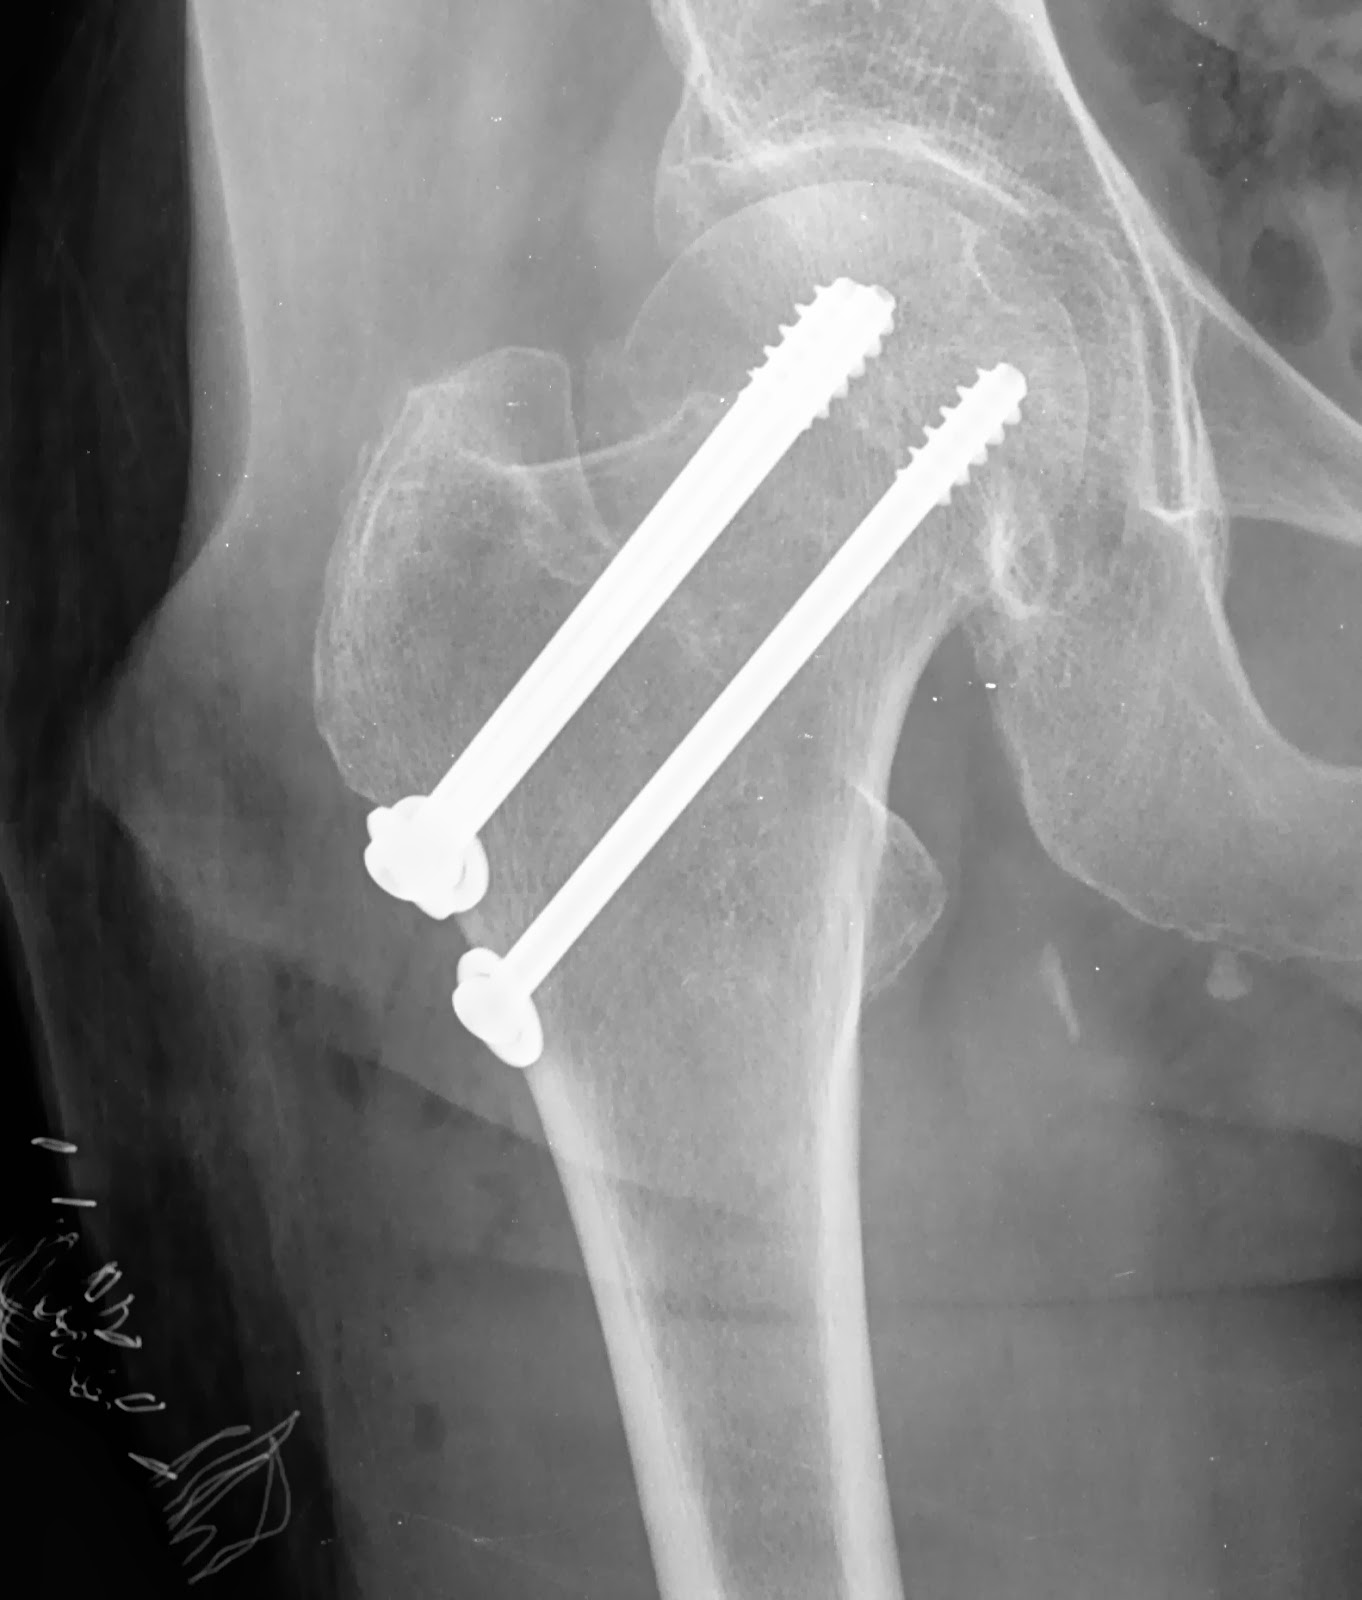

Colo do Fêmur Fratura Artroplastias

Fractura do colo do fémur a direita, tipo Garden I e seu tratamento cirurgico Enfermagem em

Fraturas do Quadril Transtrocanteriana e Colo do Fêmur